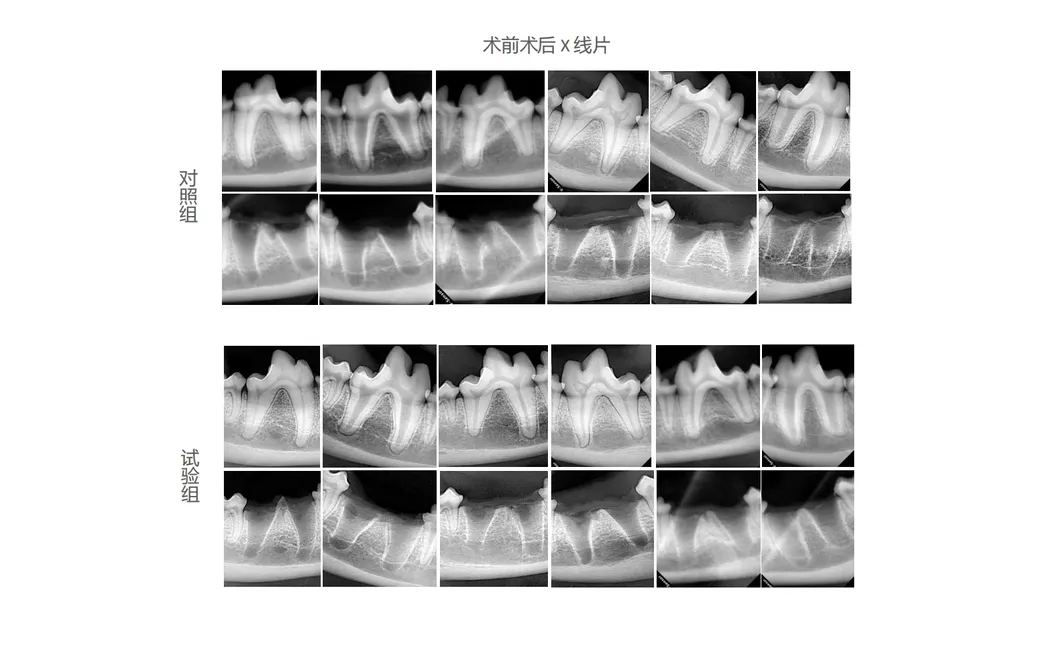

In this study, subjects were selected to analyze the effectiveness of innovative dental tools. The control group utilized traditional manual devices, while the treatment group utilized the cutting-edge Pneumatic Dental Elevator Kit. Researchers documented physiological parameters, intraoperative complications, extraction duration, and socket damage, alongside histological evaluations to confirm performance.